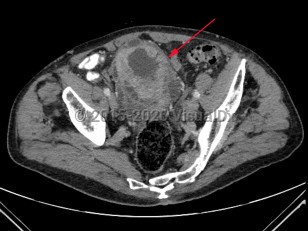

Uterine fibroidsUterine fibroids

Uterovaginal prolapse

EndometriosisEndometriosis